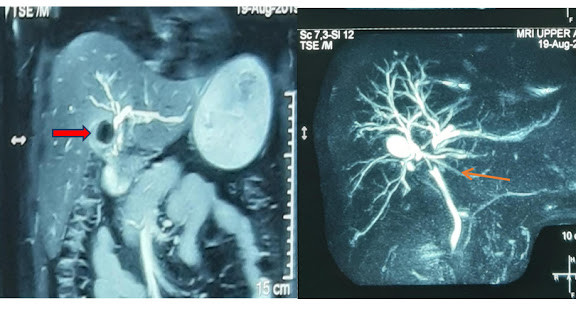

A 39 years old female was admitted with complaints of recurrent pain abdomen of many years duration. She gave a history of jaundice in the past […]